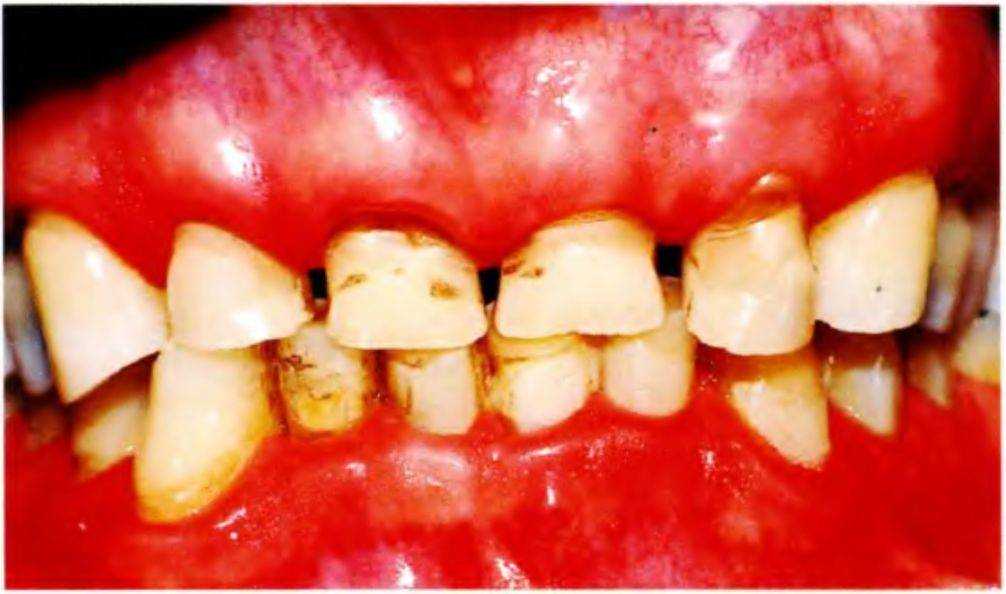

Пациент 55 лет страдает выраженным бруксизмом со значительной стираемостью зубов (рис. с 6-5а по 6-5с). Всем зубам показано восстановление с помощью коронок из-за значительной утраты твердых тканей и обнажения дентина, что сопровождается развитием гиперчувствительности. Требование пациента заключалось в создании эстетичных и функциональных реставраций.

Основной вопрос в подобных случаях заключается в степени увеличения межальвеолярного расстояния. Главное условие увеличения высоты окклюзии состоит в отсутствии патологии ВНЧС и жевательной мускулатуры, что подтверждается клиническим функциональным анализом (рис. с 6-5d по 6-5f).